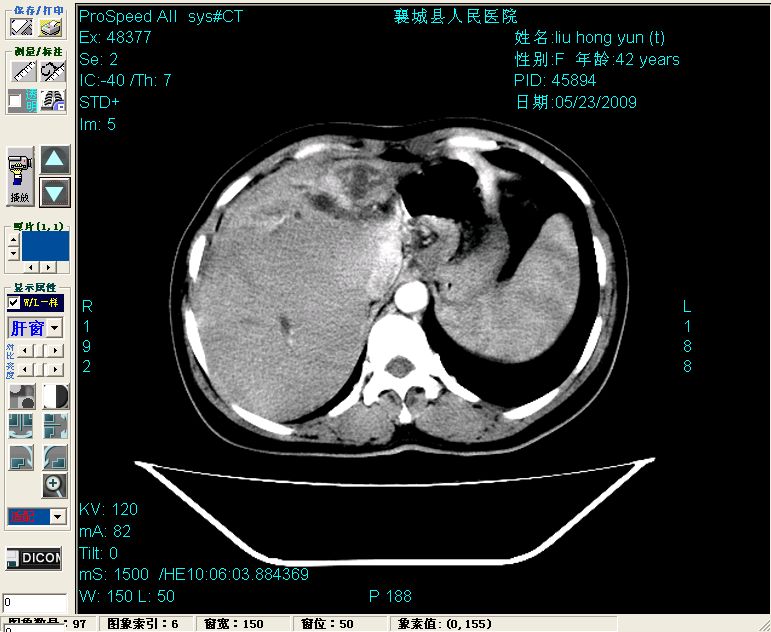

平扫:

平扫左肝外叶体积显著减小,左肝外叶见多房囊性低密度区,左肝实质及右肝前叶浅表实质呈低密度改变,左肝及右肝前叶胆管扩张,脾大

胰头部见结节状高密度影,其前方略可分辨扩强胆部管,平扫到增强始终有,但现在尚难与胃肠造影剂鉴别.

结合病史考虑,1现在引起黄疸体征的原因应该是胆总管胰段结石阻塞,建议局部胃肠造影剂排空后复查.

2左肝及右肝前叶表现考虑胆囊摘除术后所致的肝动门脉瘘形成,慢性纤维组织炎性增生.不完全除外左肝胆管细胞癌

3脾大,可能与动门脉瘘所致门脉高压有关